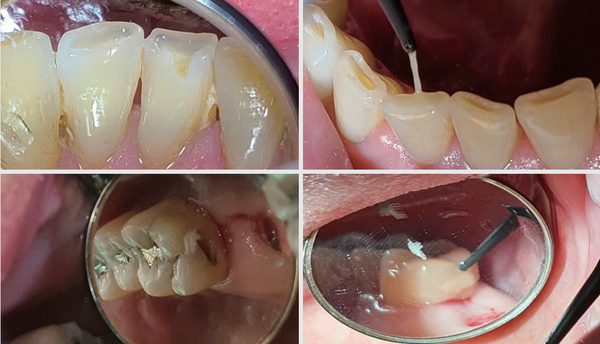

<그림>은 하악 전치부의 설측 파절이다. Attrition 후 저작 시 충격에 파절이 오는 매우 흔한 파절 부위이고 마땅히 수복할 재료도 없다. 대강 갈아서 환자에게 사용하시라고 말씀드리고 싶지만 생각보다 많이 삭제해야 하고 심미적으로 치아가 짧게 보이는 문제가생긴다. 그래서 자주 떨어져도 레진으로 붙이는게 좋다.

치아 마모 부위에 붙이는데 특화된 타사 제품은 색상이 투명하거나 너무 탁하고 시간이 많이 걸린다. 대부분 회사의 flow resin은 마진 부위가 흘러 넘쳐 두께가 두툼해진다. 흔히 사용하는 일반용 수복용 레진은 와동이 미세하기 때문에 안에 기포가 생기고 오히려 잘 떨어지고 유지를 위해 더 삭제 해야하며 시간이 많이 걸린다는 단점이 있다.

덴티움 high flow resin A2는 색상과 조작성, 그리고 시술시간까지 모두 완벽하다. 레진 침투성과 소량 수복, 적당한 내마모성이 요구 되는데 최적화된 제품이다. 또 유용한 부위는 구치부 원심 1면 우식의 경우다.

접촉부에 음식물이 낀 경우 생기는 우식은 작긴 하지만 접근이 어렵고 레진이 흘러 내리면 안에 기포가 생기고 치경부에 붙으면 광을 내다가 환자의 뺨을 다치게 하기 쉽다. 콕찍어 레진수복을 해야 편하다. 시술시간이 짧으니 입 크게 벌린 환자도 매우 만족한다.